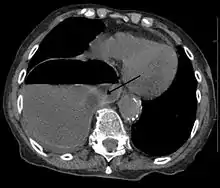

A right sided diaphragmatic hernia with the stomach in the chest (left side of image marked by the arrow). Note the air fluid level in the stomach.

Diagnosis can be made by either CT or X-ray.